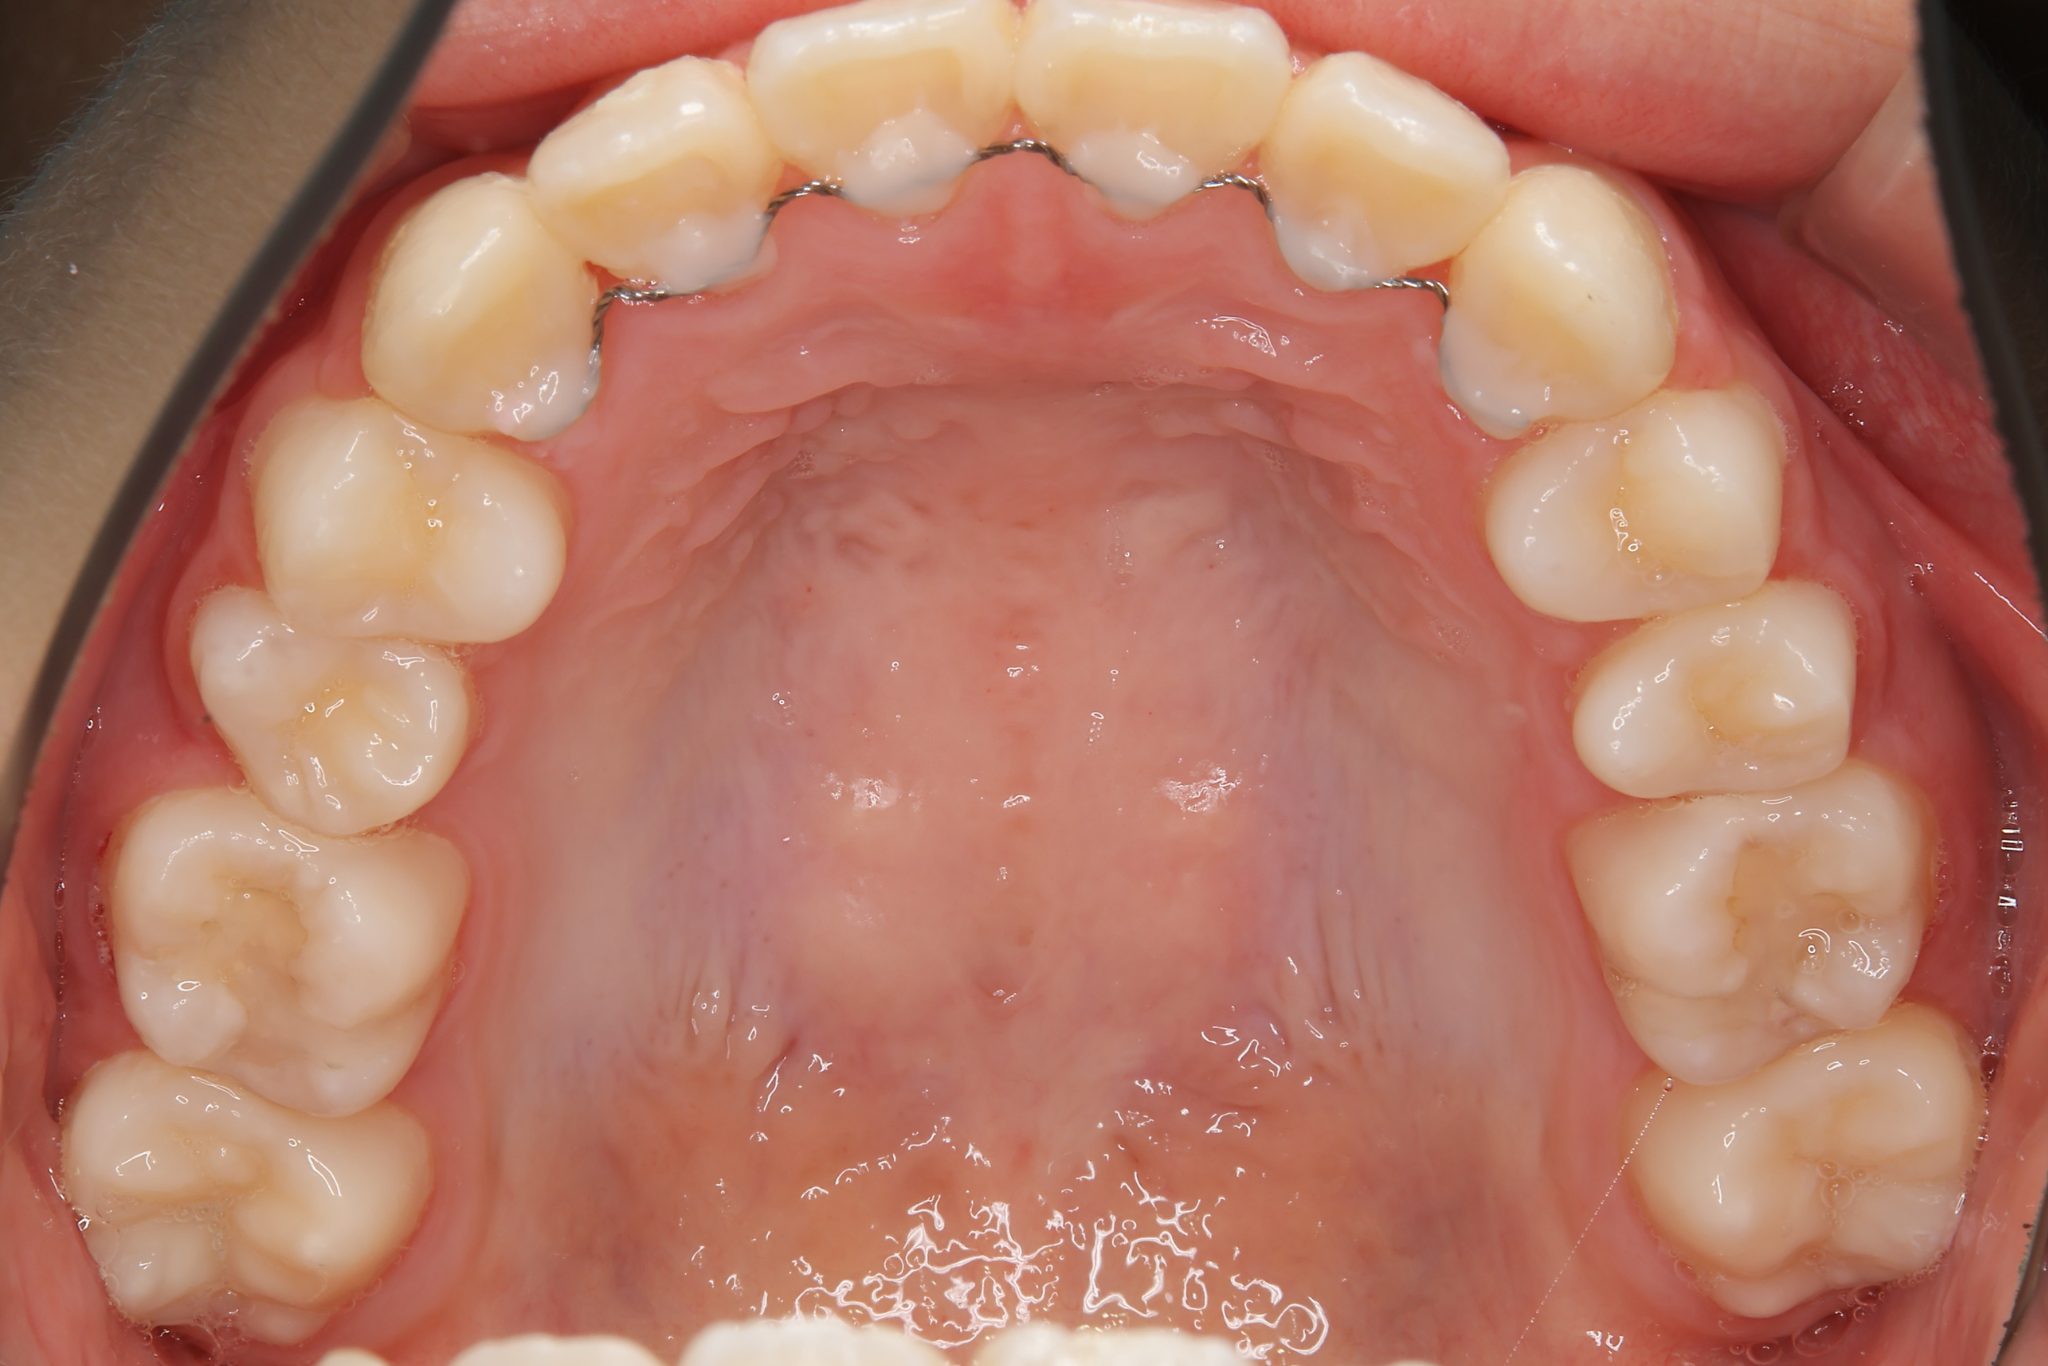

アフター

ワイヤー矯正治療|症例_1324

施術内容 MSEと下顎リンガルアーチを用いて上下顎骨を拡大した。

その後マルチブラケット装置を用いて非抜歯で歯牙を配列し、良好な咬合を獲得した。

治癒期間 1年5か月間